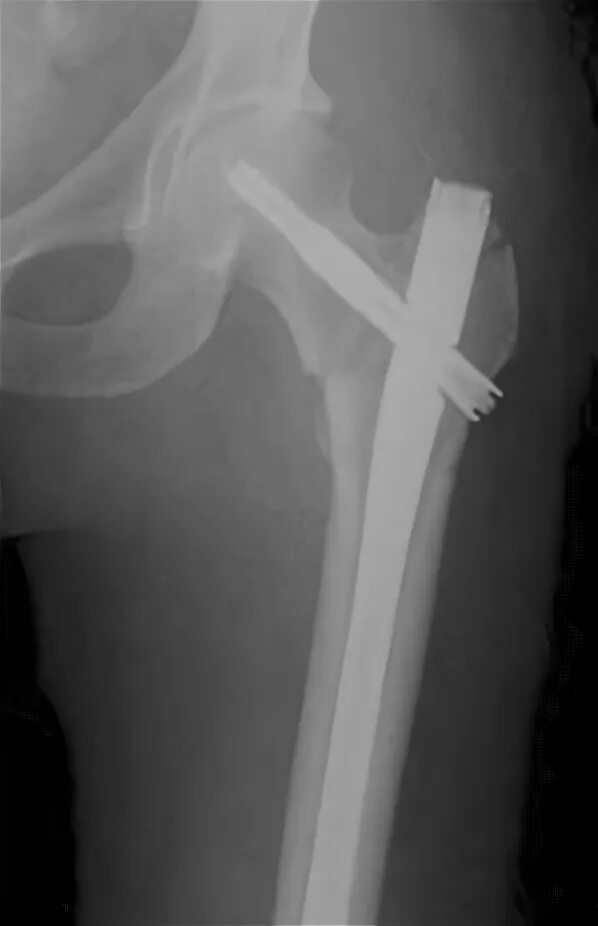

Остеосинтез чрезвертельного перелома